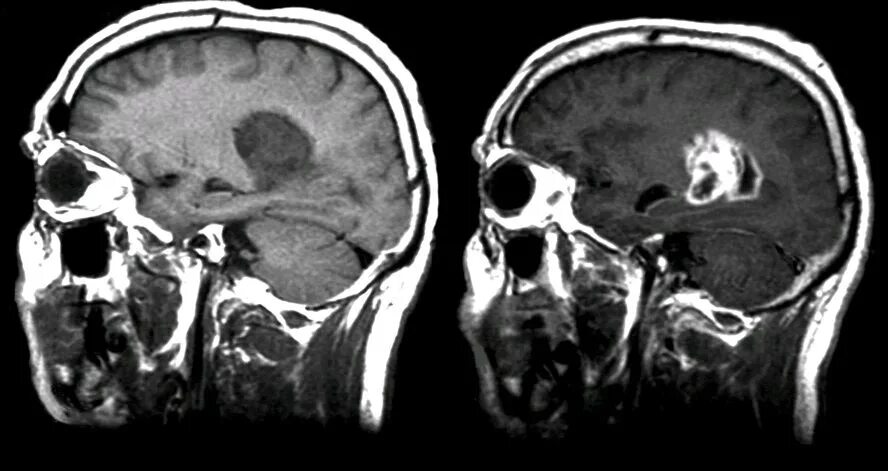

Что покажет мрт головного мозга с контрастом